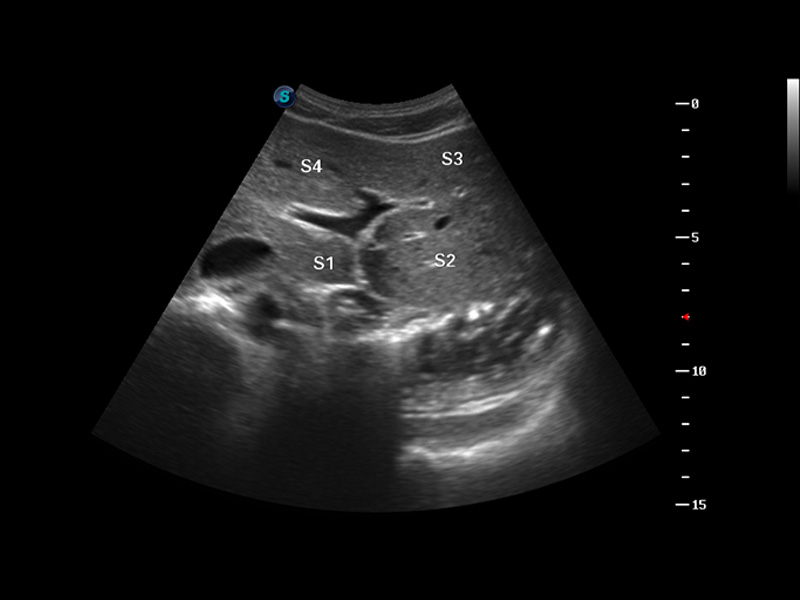

S8 EXP便携式彩色多普勒超声诊断仪是新葡的京集团8814检测站研发的高端全身应用型便携彩超。高通道的VIS平台融合可视化(Visual)、智能化(Intelligent)和人性化(Smart)的特点,配以新葡的京集团8814检测站自主研发生产的探头大家族,使您能够快速、准确的获得病人信息,提高工作效率的同时减轻疲劳。

3D/4D成像